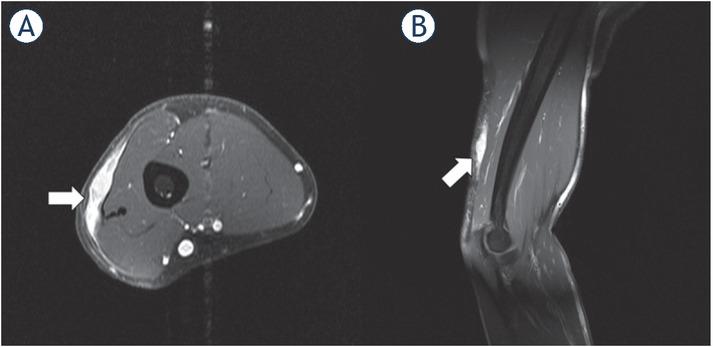

Figure 6

1.5-T MRI of the upper arm